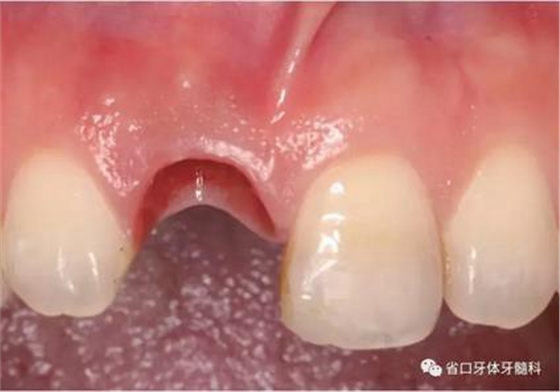

圖5 微創(chuàng)拔牙

圖6 微創(chuàng)拔牙

(1)微創(chuàng)拔牙及即刻種植:術(shù)前拍攝口內(nèi)照及實(shí)施牙周基礎(chǔ)治療。常 規(guī)消毒鋪巾阿替卡因局麻下微創(chuàng)拔除上頜右側(cè)中切牙,搔刮拔牙窩及根尖肉 芽組織。探測牙槽骨唇側(cè)骨壁及鄰面牙槽嵴完整,牙齦無撕裂。不翻瓣下于上頜右側(cè)中切牙缺隙近遠(yuǎn)中中點(diǎn)的腭側(cè)牙槽骨及根方定位,按照逐級預(yù)備的原則,緊貼牙槽窩腭側(cè)骨壁制備種植窩洞,植入Zimer®3.7mm×13mm TSV種植體1顆,植入扭矩>35N·cm,以O(shè)sstell測量種植體的ISQ值為68。 種植體平臺位于唇側(cè)齦緣中點(diǎn)下3mm,與唇側(cè)骨壁內(nèi)側(cè)面形成的跳躍間 隙約2mm,置入Bio-Oss®細(xì)顆粒骨粉0.25g,上愈合基臺關(guān)閉創(chuàng)口。術(shù)后 CBCT檢查顯示:種植體利用牙槽窩根方骨質(zhì)固位,緊貼牙槽窩腭側(cè)骨壁, 其唇側(cè)面與牙槽窩唇側(cè)骨壁的內(nèi)側(cè)面所形成的跳躍間隙(約2mm)可見顆 粒狀顯影物充填。牙槽窩的唇側(cè)骨壁及唇側(cè)倒凹無缺損穿孔。